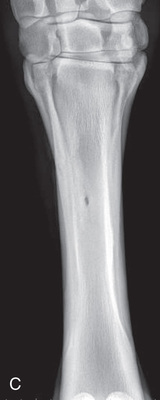

| Metacarpal/metatarsal cannon bone (M3) | Dorsoproximal-palmarodistal (DPr-PaDi) | Dorsopalmar (DP) |

| Lateromedial (LM) | Lateral (L) | |

| Lateral splint bone (M4) | Dorsoproximal 45-degree lateral–palmarodistomedial oblique (DPr45L-PaDiMO) | DLPMO |

| Medial splint bone (M2) | Dorsoproximal 45-degree medial–palmarodistolateral oblique (DPr45M-PaDiLO) | DMPLO |